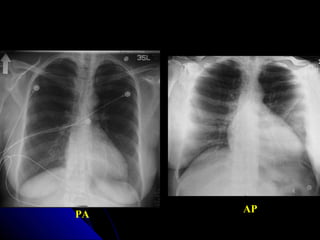

OOrriieennttaattiioonn

TThhee uussuuaall iinnddiiccaattiioonn ffoorr AAPP iiss aa ppaattiieenntt

wwhhoo iiss ccoonnffiinneedd ttoo bbeedd.. IIff iinn ddoouubbtt,, llooookk aatt

tthhee rreellaattiioonnsshhiipp ooff tthhee ssccaappuullaaee ttoo tthhee lluunngg

mmaarrggiinnss.. AA PPAA vviieeww sshhoowwss tthhee ssccaappuullaaee

cclleeaarr ooff tthhee lluunnggss wwhhiillsstt iinn AAPP pprroojjeeccttiioonn

tthheeyy aallmmoosstt aallwwaayyss oovveerrllaapp.. TThhee ccaarrddiiaacc

sshhaaddooww llooookkss bbiiggggeerr oonn aann AAPP vviieeww..

PA AP

16 OOrriieennttaattiioonn TThheeuussuuaall iinnddiiccaattiioonn ffoorr AAPP iiss aa ppaattiieenntt wwhhoo iiss ccoonnffiinneedd ttoo bbeedd.. IIff iinn ddoouubbtt,, llooookk aatt tthhee rreellaattiioonnsshhiipp ooff tthhee ssccaappuullaaee ttoo tthhee lluunngg mmaarrggiinnss.. AA PPAA vviieeww sshhoowwss tthhee ssccaappuullaaee cclleeaarr ooff tthhee lluunnggss wwhhiillsstt iinn AAPP pprroojjeeccttiioonn tthheeyy aallmmoosstt aallwwaayyss oovveerrllaapp.. TThhee ccaarrddiiaacc sshhaaddooww llooookkss bbiiggggeerr oonn aann AAPP vviieeww..